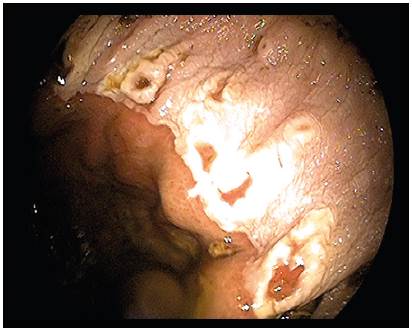

The frequency of EGUS in the population was 69%. In the stabled animals, a wide variety of lesions were found at endoscopy, with gastritis being the most frequent finding (36%), followed by hyperkeratosis of the MP (25%), and hyperemia of this same region (17%). Other lesions found in other gastric regions are described in Table 2, some of which corresponded to superficial lesions of the pyloric antrum (Figure 1) or severe ulceration in the MP (Figure 2). For grazing animals, 49% of observations were absent. Within the lesions found in this group of animals, MP hyperkeratosis was the most common (38%; Table 2). During endoscopy, no lesions affecting the esophagus were observed.

Figure 2 Endoscopic image of MP (minor curvature) of a studied equine. Evidence of localized ulcerative lesions. Category 5/5 (regarding severity) according to MacAllister et al. (1997).